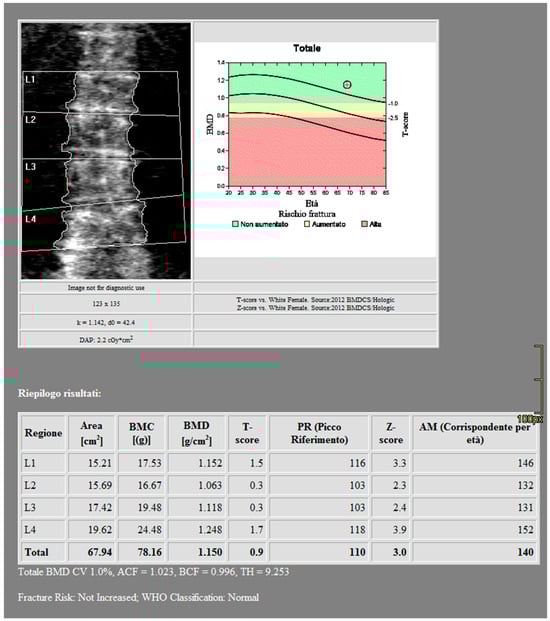

CT images were processed using AW3.2 software (GE Healthcare, Chicago, IL, USA) with a bone window and HAP–fat base material pairing, which highlights structures containing hydroxyapatite. Three-dimensional volume of interest (VOI) measurements were obtained at the lumbar vertebrae (Figure 3) and femoral neck (Figure 4), sampling the trabecular bone while excluding cortical bone regions.

Figure 3. DECT measurements on the lumbar vertebrae (ROI1: L4 measurement; ROI2: L3 measurement; ROI3: L2 measurement; ROI4: L1 measurement). The ROI volume was 858 mm3.